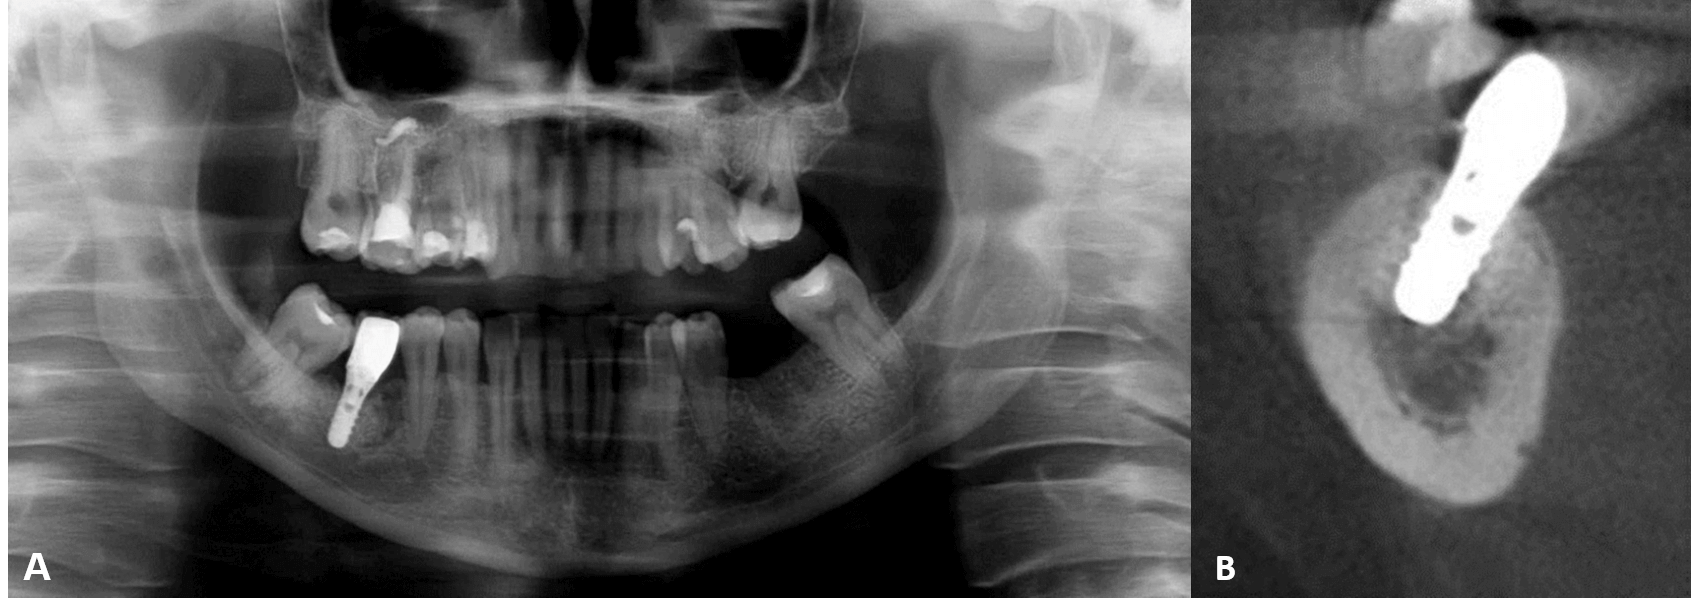

Fig.1

El tratamiento consta en rellenar el foco osteoporótico con sustituto óseo y atornillar el implante a nivel tisular, que tiene un cuello y un hombro. Se eligió este tratamiento para evitar posibles complicaciones relacionadas con la lesión del nervio alveolar inferior y el desplazamiento del implante hacia la médula ósea mandibular. Algunos autores presentaron datos sobre el desplazamiento accidental del implante hacia el espacio medular del cuerpo mandibular en pacientes con defecto óseo medular osteoporótico focal. El desplazamiento importante del implante puede causar principalmente la compresión o incluso la lesión del nervio alveolar inferior. La situación puede complicarse con una nueva intervención quirúrgica para la extracción de los implantes, durante la cual pueden producirse lesiones secundarias en el nervio. La mayoría de los autores de los casos presentados utilizaron implantes a nivel óseo que no estaban suficientemente fijados en la capa cortical de la mandíbula. Por el contrario, en este estudio se utilizó un implante a nivel del tejido con un reborde prominente.

Iwanaga y sus coautores investigaron la anatomía microquirúrgica de la pared superior del canal mandibular y el patrón óseo esponjoso por encima del canal mandibular. La vista inferior del canal se clasificó en cuatro grupos en función de la superficie de la pared superior del canal mandibular. En el caso de la clase II, la pared superior del canal mandibular era osteoporótica y, al rellenar con demasiada fuerza el defecto de la médula ósea osteoporótica, los gránulos del sustituto óseo podían penetrar en el canal mandibular. Esto puede provocar una complicación grave: la compresión del nervio alveolar inferior. Por eso, el relleno del defecto óseo debe realizarse con suavidad, sin presión, dando forma al alveolo del implante con un medidor de profundidad, antes de atornillar el implante. Es importante señalar que es necesario asegurarse de que el sustituto óseo rellene la cavidad entre las paredes bucal y lingual, para garantizar el relleno bicortical del defecto.